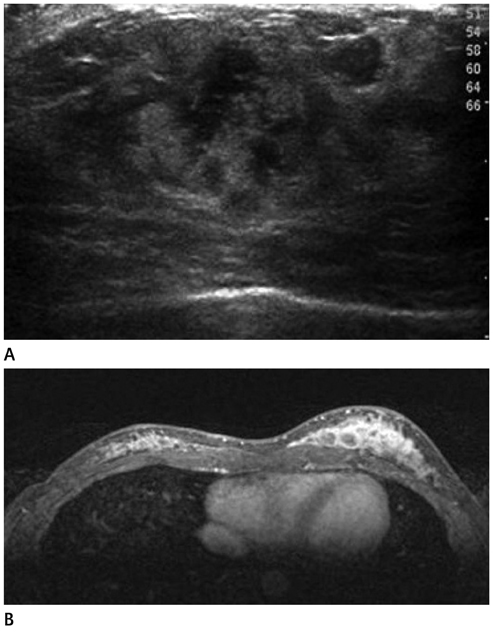

- The purpose of this study is to review various breast diseases in children and adolescents and to illustrate the sonographic findings. We reviewed the cases at our institution in order to identify breast disease in children and adolescent patients who underwent sonography and mammography. Breast disease in children and adolescents included developmental disturbance, infection, benign tumors and inherent defects. In contrast to adults, the radiologic findings of malignant breast conditions in pediatric populations have rarely been reported; however, we show ductal carcinoma in situ with juvenile fibroadenoma and rhabdomyosarcoma. During childhood and adolescence, the recognition and correct identification of physiologic breast development and specific lesions in breast entities on radiologic findings is most helpful in identifying and characterizing abnormalities and in guiding further investigation.